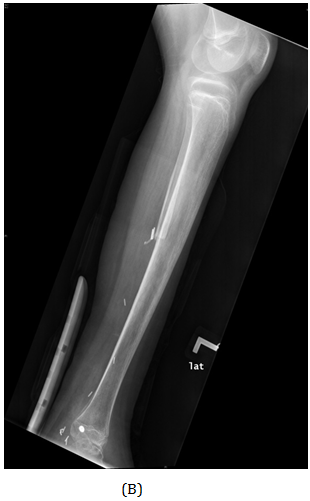

Figure 1 AP view of plain X-ray of the left leg showed ill-defined lesion involved distal end of the fibula (diaphysis) with cortical destruction and soft tissues swelling.

A girl, 11yearsold Saudi presented to us with progressive swelling of the left lower limb, localized above the left ankle with complaints of pain and limping gait. She had visited many clinics for her pain and swelling with no relief to her symptoms. The patient was examined clinically and there was a swelling in the lateral aspect of the distal leg tender firm too hard with intact skin over it, 4x3 cm, no other systemic clinical finding of note. X-ray of the left leg (Figure 1) showed aggressive lytic lesion of the distal fibula. Thence patient was investigated with basic lab works plus systemic and local staging for further diagnosis. She was admitted under us in pediatric surgical ward for open biopsy of the distal fibular lesion and CT of the lower limb (Figure 2) showed destructive bone lesion involving the distal end of the fibula associated with extensive destruction and aggressive periosteal reaction associated with large soft tissue mass 4.5 x 5 cm in maximum axial dimension. Also, MRI of the lower limb (Figure 3) showed there is a large destructive bone lesion involving the distal diaphysis of the left fibula. This lesion does not cross the growth plate. It is associated with aggressive periosteal reaction along with a large soft tissue mass that appears of high signal intensity in T2 and intermediate to low signal intensity in T1 sequences. This was followed by technetium-99m MDP scintigraphy (Figure 4), it showed an increased tracer uptake in the distal left fibula, extending to the left ankle and the left foot. Excisional biopsy was taken from the proximal and distal margin of the lesion in the left fibula which confirmed Ewing's Sarcoma. According to the histopathology department, they reported that there is no evidence of residual tumor i.e free resection margins. (Figure 5) The patient was referred from us to pediatric oncology clinic for further evaluation. She was electively admitted to the hospital for staging and central line insertion to start chemotherapy. She treated as per Ewing sarcoma protocol in our hospital. Patient was put on neoadjuvant chemotherapy which included vincristine, cyclophosphamide, doxorubicin and etoposide, and if osfamide 3 times weekly. After 6 months of chemotherapy, we recommend to her family to do a surgery. We did a wide surgical resection of the tumor in the left leg. Subcutaneous tissue was dissected and isolation of superficial peroneal nerve was done. Dissection of lateral compartment of the left leg up to 16cm proximal to the lateral malleolus and distally, until the distal physis (Figure 6). The tendons of the peroneus longus, peroneus brevis, and flexor halluces longus were sacrificed and the ruminants were used to reconstruct for the lateral aspect of the left ankle using suture anchors (Figure 7). K-wires were used to do temporary arthrodesis (Figure 8). The surgical wound was closed in layers. VAC dressing was also applied as standard care management in Oncology cases at KFMC and backs lab was applied (Figure 9). The last MRI done for the patient showed there is altered signal intensity of the soft tissue with post-contrast enhancement. However, the dimensions of this area of altered signal intensity are decreased as compared to previous MRI. There is no evidence of soft tissue mass lesion (Figure 10). According to the last patient's follow up after six months post-operation it shows no Valgus deviation, normal ankle motion, mobilizing full weight bearing with splint assistant during physical examination (Figure 11). Also, X-rays and MRI finding shows no residual mass lesion or local recurrence.